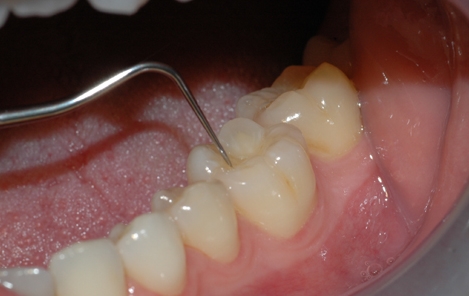

Tannkjøttet og tennenes benfeste blir vurdert

Tannlegen undersøker hver enkelt tann etter hull og skader